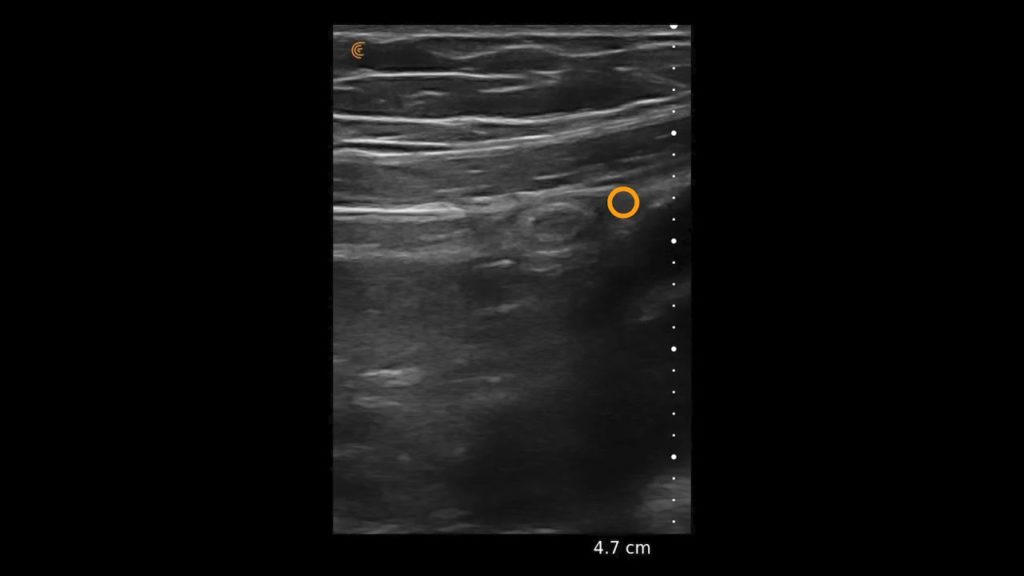

Canine Jejunal Lymph Nodes

Using the jejunum as an important landmark, the hypoechoic jejunal lymph nodes can be identified. In this video Dr. Edwards explains the ultrasound appearance of normal jejunal nodes.